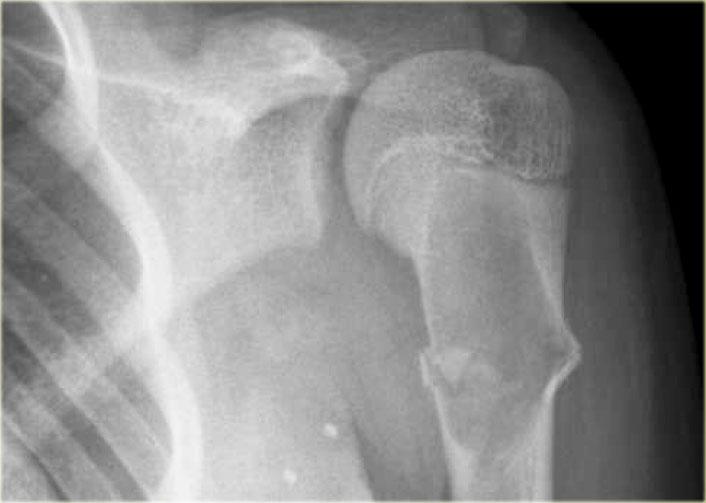

SBC: well-defined osteolytic lesion without expansion of the proximal meta-diaphysis of the humerus with pathologic fracture

Solitary Bone Cyst

Nang xương đơn độc, còn được gọi là nang xương đơn buồng, là một nang xương thực sự.

Nhiều tổn thương tiêu xương giới hạn rõ thường được gọi là dạng nang, nhưng đây là cách gọi không chính xác.

Nang xương đơn độc thường biểu hiện bằng gãy xương.

Đôi khi có thể thấy hình ảnh mảnh xương gãy rơi xuống (fallen fragment).

Vị trí hay gặp: đầu trên xương cánh tay và xương đùi.

Thường ít giãn nở hơn so với nang xương phình mạch.

Chẩn đoán phân biệt: nang xương phình mạch, loạn sản xơ dạng nang.

Nang xương đơn độc có thể di chuyển từ vùng hành xương đến thân xương trong quá trình phát triển của xương.

Discriminators:

- Must be under age 30.

- Must be centric